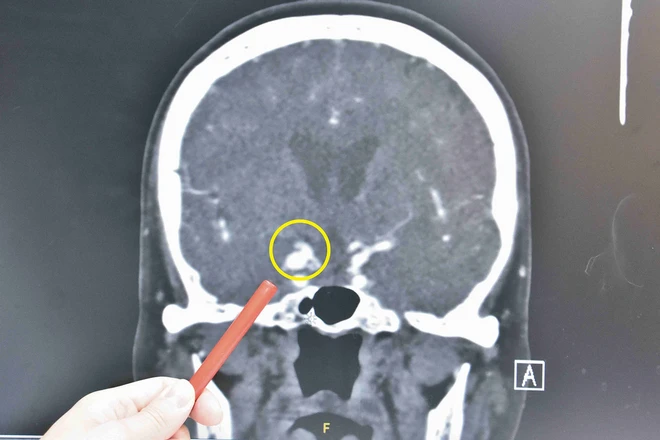

眼皮下垂、畏光恐是腦神經受壓迫!80歲曾婆婆頭暈目眩雙眼複視、畏光,經眼科診所治療後不僅未改善,甚至呈現「睁一隻眼閉一隻眼」的狀態,經轉診至彰基醫學中心神經外科門診,發現長達8豪米「顱內動脈瘤」,造成動眼神經壓迫,經開顱動脈瘤夾除手術後,右眼皮可以張開,右眼轉動也漸漸恢復正常,畏光與複視重影症狀也獲改善。

顱內動脈瘤是潛伏性的殺手,絕大部分患者終其一生是無症狀的,除了少數如曾婆婆的動脈瘤有壓迫到視神經或動眼神經,在破裂出血造成昏迷前及時發現,可以早期處理,大部分的病患往往是已經破裂而造成劇烈頭痛、意識不清才緊急送醫。

曾婆婆的動脈瘤有壓迫到視神經或動眼神經,在破裂出血造成昏迷前及時發現,可以早期處理。(圖片來源:彰基醫學中心。)